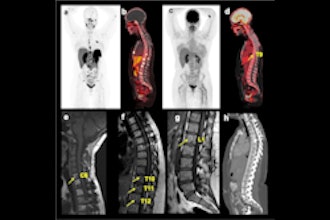

Cases of the Week

Check out our Cases of the Week!